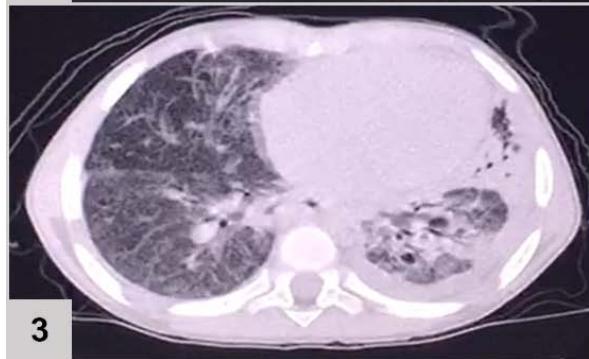

Computerized tomography (CT) of the chest (FIGURE 1)

Figure 1: CT of the chest results: extensive consolidation, with air bronchograms and cystic images in between, in the left lung (3 and 4); ground-glass opacities, diffusion in the lower left lobe (1 and 2); nodular opacity, no sign of calcification in between, on both lungs (1, 2 and 3); reticular and linear opacity and parenchymal bands in the upper lobes (3 and 4); small pleural effusion on the left (1 and 2); adjacent subsegmental atelectasis (2 and 4)

The patient's chest CT scan for the evaluation of pulmonary zygomycosis showed suggestive findings of fungal balls in both lungs, visualized as non-calcified nodular opacities and pleural effusion on the left, which is an infrequent radiological sign[^6], but of great importance for diagnosis, because the mutual presence of multiple fungal balls with pleural effusion are independent predictors of pulmonary zygomycosis[^5].